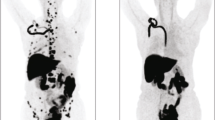

Imaging Results

Imaging examples from two patients are provided (Fig. 1). Both patients had lymph node metastases from ER+ breast cancer. Patient A (15-002) whose axillary mass biopsy demonstrated ER positivity had high FES uptake at each site identified on FDG-PET. Patient B (3-001) whose T10 vertebral lesion tumor biopsy was ER- had nodal metastases clearly visualized on FDG-PET, but not appreciated by FES-PET.

Imaging examples from two patients who underwent both FES and FDG scans prior to therapy. Left panel: Patient A (15-002) had mediastinal lesions appreciated by both FES and FDG. Right panel: Patient B (3-001) also had mediastinal disease clearly seen by FDG-PET, not visible on FES-PET. The core biopsy of a metastatic axillary lesion from Patient A showed ER + breast cancer, while the needle biopsy of a vertebral lesion from Patient B showed ER- breast cancer.